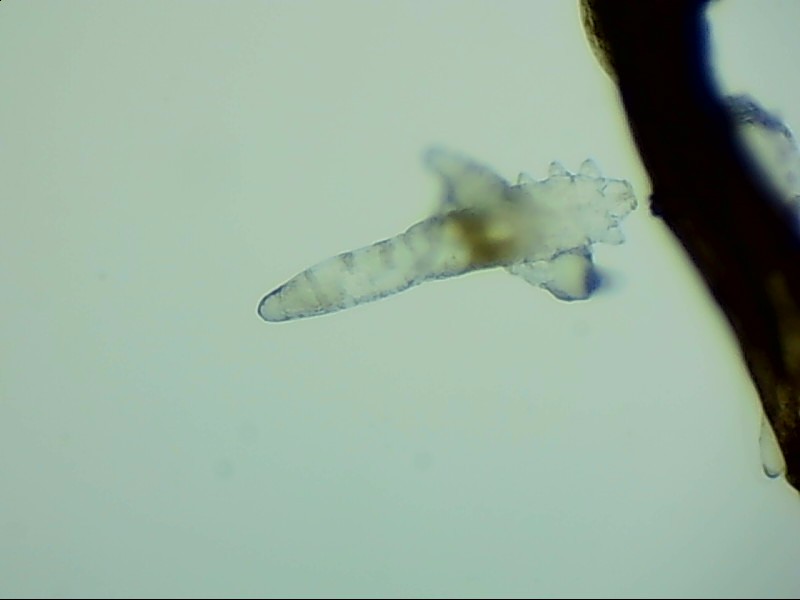

螨蟲鏡檢主要是通過顯微鏡觀察,它能無死角放大你的睫毛,讓螨蟲無處可躲。

在檢查的時候,醫(yī)生要在每個眼瞼上拔出幾根比較典型的睫毛,然后放在光學(xué)顯微鏡下,尋找有沒有螨蟲,同時觀察螨蟲的數(shù)量多少。

蠕形螨完全長大也只有0.1-0.2毫米,因此肉眼難以看到它們,只有在電子顯微鏡下我們才能看到睫毛根部的一只只蠕形螨。這些螨蟲每天都很活躍,且繁殖速度極快,完成一代生活史僅需大概15天。